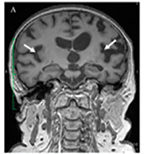

Пример МРТ |

аППА |

Наличие аграмматизма. Нарушение беглости речи. Оральная апраксия |

Атрофические изменения в нижней лобной извилине (зона Брока) и островковой коры левого полушария |

|